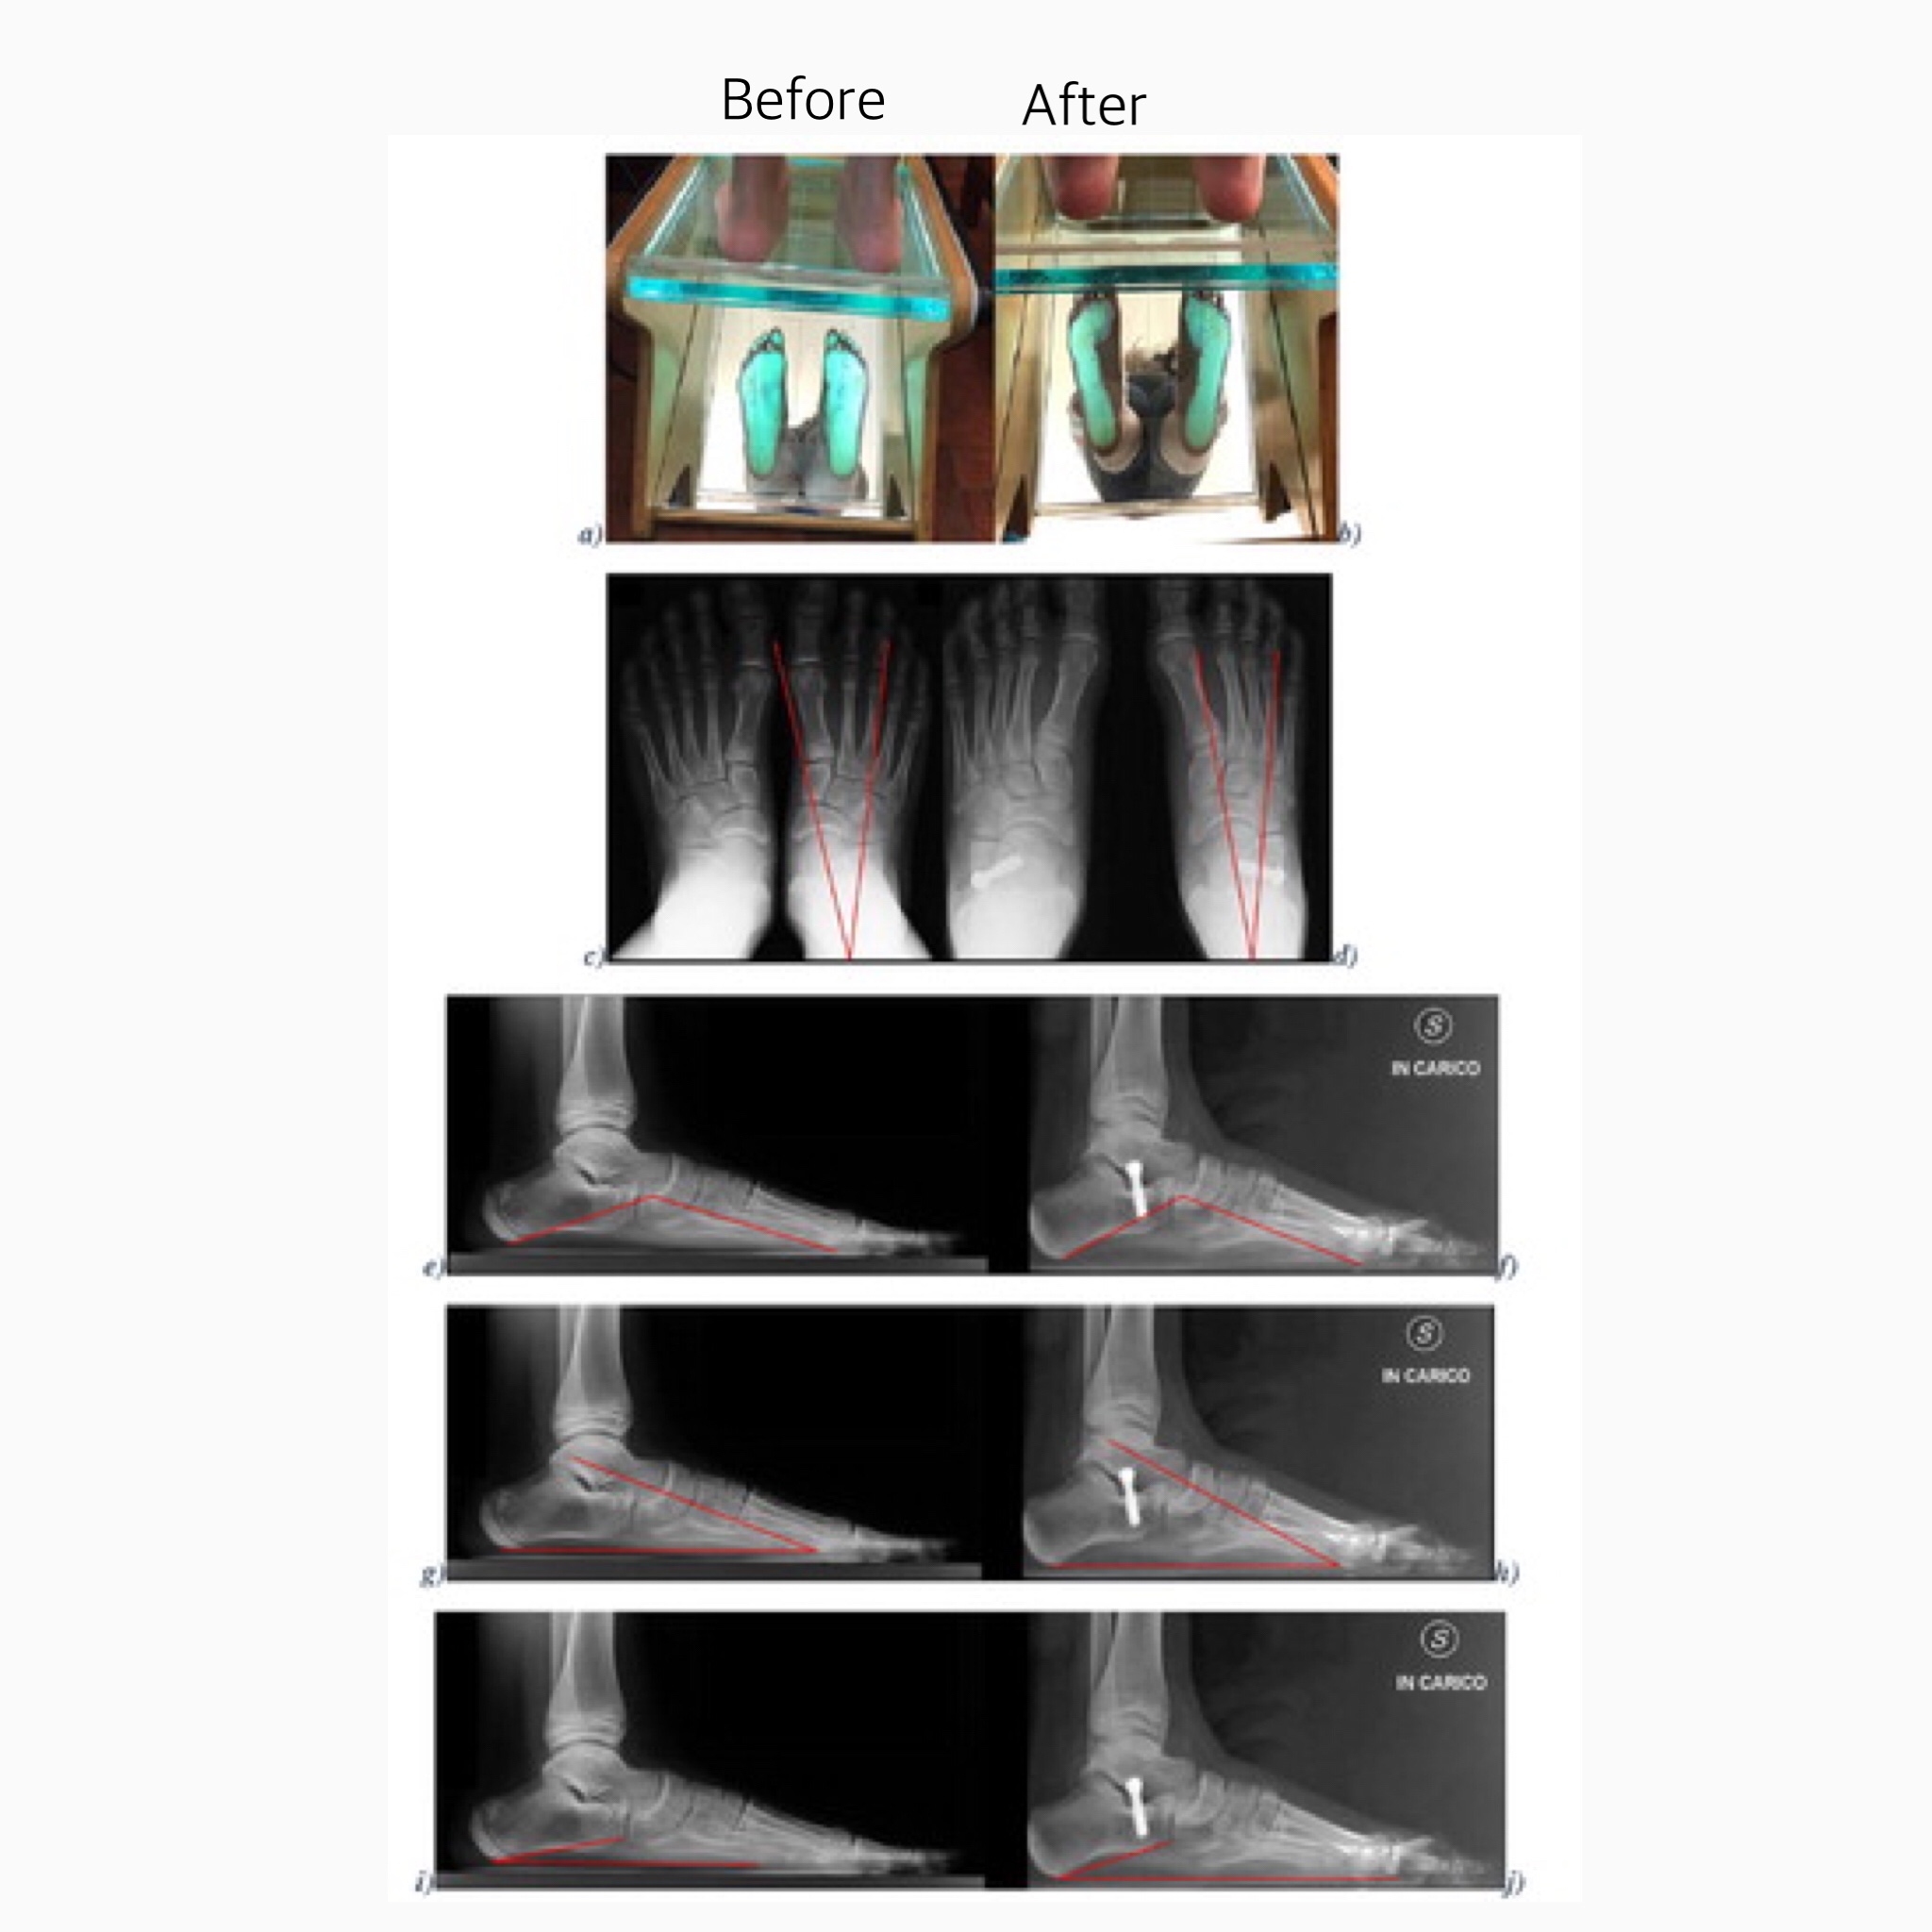

The calcaneus stop is a cheap, simple and effective technique to correct symptomatic childhood flexible flat feet that have not responded to conservative measures. The technique corrects the foot in the short term and this correction is maintained over time.

The screws are platinum coated and placed between two bones helping to displace the bone that holds the arch of the flat feet. The screws are kept for about two years inside the body, when walking the screws deviate the bones making the arch of the foot shape.

Sometimes the arch of the foot is too flat and the surgeon may decide to put one more screw or change to a longer one two years later.